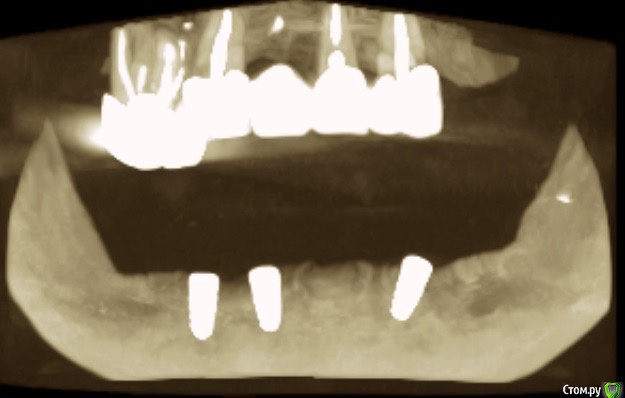

Andre_ Опубликовано 17 марта, 2016 Поделиться Опубликовано 17 марта, 2016 Из анамнеза : Ж, 25 лет, HCv, финансы на зубы лимитированы. Фото 1 до, фото 2 и 3 - около 5 мес. Ортопед хотел/хочет шаровидные абатменты и условно съёмный. Фото во рту утеряно, простит : Биотип тонкий, в позиции 3.3 вместе с шурупом НКР, успешно сьедено, вторичке. Сейчас шея и витки светятся через слизистую. Подвижная слизистая начинается по вершине гребня. Цель - изобразить пкд вокруг имплантов, что посоветуете? Есть смысл углублять преддверие, если да - как? Буду признателен совету, пока план дальнейших действий невразумительный. Ссылка на комментарий